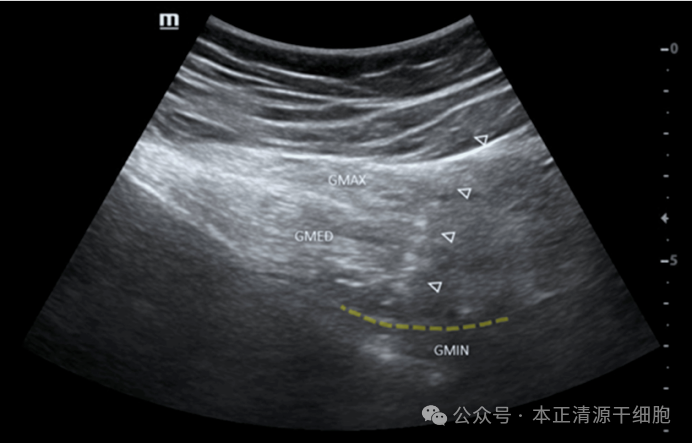

| 周围神经损伤是长期困扰临床的一大难题,其导致的顽固性疼痛与运动功能障碍,往往使患者陷入漫长的康复困境。传统疗法效果有限,但再生医学的进展,尤其是间充质干细胞疗法的应用,正为这类损伤的修复带来全新希望。本文将通过一则发表于Cureus期刊的最新案例,展现其在治疗严重神经损伤中的惊人潜力。案例中的患者为一位71岁女性,因重度髋关节炎接受全髋关节置换术后,出现了严重的臀上神经损伤并发症。术后她持续经历烧灼性神经性疼痛,疼痛评分达到极限的10分,同时臀肌肌力和敏感度下降,行走和日常活动完全依赖助行器。尽管后续接受了包括再次手术、长期抗生素治疗及系统康复训练,历时一年余,其功能仍无显著改善,生活备受困扰。2024年4月,肌电图检查明确显示臀上神经存在轴突损伤,其控制的臀中肌与臀小肌表现出神经功能丧失的特征,但同时也检测到神经正在尝试重新生长的早期信号。鉴于常规治疗无效,医疗团队决定采用创新性的间充质干细胞进行治疗。治疗于2024年6月实施。在超声实时精确引导下,将制备好的细胞悬液注射到目标神经损伤区域,即臀中肌和臀小肌之间的平面。图1:超声图像显示MSCs浸润至臀小肌与臀中肌之间的筋膜层疗效评估在治疗后60天进行。肌电图复查结果令人振奋:此前清晰的神经损伤迹象已完全消失,神经传导恢复正常。患者的自觉症状同步大幅改善:疼痛评分从10分降至3分。运动功能客观检测数据更为显著:· 右髋伸展力量测试中,最大扭矩提升55%,最大功率提升9%。· 右髋屈曲力量测试显示,最大扭矩增加24%,最大功率显著增长93%,总做功能力增加58焦耳。图2: 髋部伸展的等速动图:扭矩(牛顿米)×角度(度数)图(a)于2024年4月11日MSC浸透前进行,图(b)于2024年8月26日浸透后进行。(蓝线表示右髋关节,红线表示左髋关节。)这些数据共同表明,髋关节周围肌力、肌肉做功效率及整体运动功能均获得实质性提升。患者步行能力改善,对辅助设备的依赖减轻,日常生活质量得到显著恢复。该案例证实,间充质干细胞能有效促进周围神经结构与功能的修复,其作用机制是多方面的,主要基于干细胞的旁分泌功能与免疫调节特性。它们通过释放神经营养因子支持神经元存活与轴突再生,同时调控损伤局部的免疫反应、减轻炎症与纤维化,从而优化神经修复的微环境。此外,干细胞还具有向神经支持细胞分化的潜能,可参与髓鞘重塑,进一步促进结构与功能的恢复。这一成功案例不仅为周围神经损伤治疗提供了新思路,也反映了再生医学更广泛的潜力。间充质干细胞凭借其多向分化、组织修复及免疫调节等特性,在神经系统疾病、骨关节修复、心血管疾病等多个领域展现出广阔的应用前景。随着未来研究的深入与技术的规范化,细胞疗法有望为更多难治性疾病带来突破性的治疗选择。